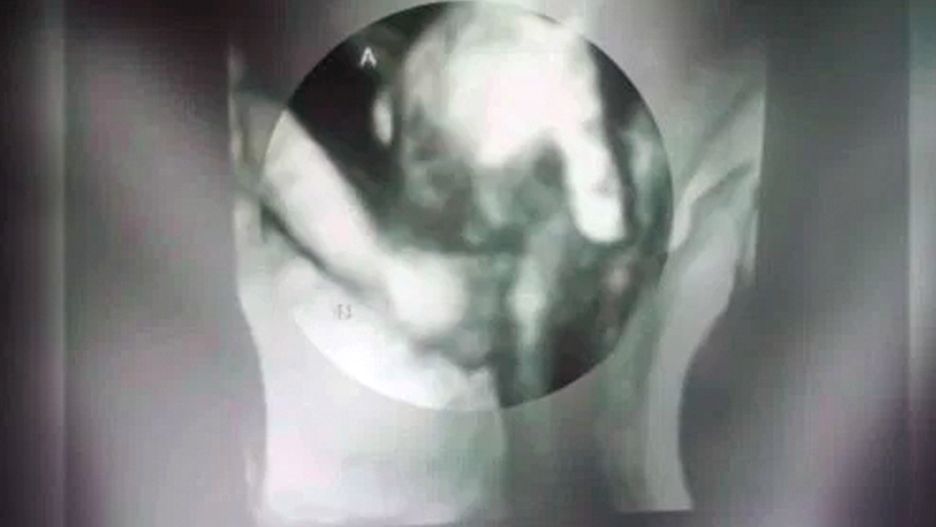

Normalnie rozwijająca się dziewczynka trzyma swojego upośledzonego brata za rękę. Rodzice bliźniaków pokazali wzruszające zdjęcie z USG.

Ian i Brittani McIntire mieli zostać rodzicami bliźniaków. Niestety, wraz z kolejnym okresowym badaniem USG dostali smutną wiadomość. Brat i siostra nie rozwijali się jednakowo dobrze. Dziewczynka była okazem zdrowia i ważyła 900 g. Chłopiec ważył jedynie 255 g, miał dziurę w sercu i niepoprawnie wykształcony mózg.

Z każdej kolejnej wizyty wracali bardziej smutni. Dopiero podczas ostatniej ukoili nieco żal. Fotografia wykonana podczas badania ultrasonografem zdaje się pokazywać coś równie niezwykłego, jak wzruszającego.

Większość bliźniaków w trakcie badań USG kopie się nawzajem, a nasza córka zdawała się bronić brata. Wygląda, jakby trzymała go za rękę. Jego mała dłoń łapie za jeden z jej palców - przekonuje Birttani.

Dla rodziców sonogram jest jakimś pocieszeniem i ważną pamiątką. Chłopiec pewnie nigdy nie pozna swoich rodziców ani siostry poza brzuchem matki.